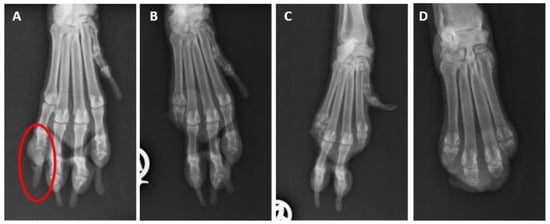

Figure 7. X-rays of the right front paw of a male standard schnauzer. (A): The osteolysis (circle) of the distal phalanx of digit 5 at the age of 9 years. (B): Status after amputation of the distal phalanx of digit 5 at the age of 9 years. (C): Status after the amputations of digits 2 and 5 at the age of 10 years. (D): Status after the amputation of all five digits at the age of 11 years. The © images were kindly provided by Dr. Andreas Haag, Mannheim, Germany.

In 54 dogs (21 GSs and 33 SSs), multiple dSCCs (2 to 6 affected toes) were reported. Multiplicity was significantly more common in the SSs (18.7%) than in the GSs (9.3%; p = 0.003; Figure 6). In our cohort, more than four affected digits were documented in the SSs alone (n = 4). When multiple dSCCs occurred, they were mostly located on different limbs but there were single cases with multiple affected toes on one leg (Figure 7).

For 46 dogs (18 GSs and 28 SSs) with multiple SCCs of the toes, the disease-free intervals were available. The disease-free intervals did not differ significantly between the GSs and SSs (p = 0.91). The time between the first and second dSCC ranged from 1 to 27 months in the GSs (median 13 months) and from 1 to 30 months in the SSs (median 12 months). A third toe was affected 1 to 25 months later (GS: n = 5, median 15 months; SS: n = 8, median 9 months). In one GS, a fourth toe developed digital SCC one month later. In four male black SSs, a fourth digit was affected 3 to 19 months later (median 7.5). Two of these dogs had dSCCs on a fifth digit 16 and 19 months later, respectively. One dog had lost six digits within 5 years due to dSCC and was euthanised at the age of 13 years because of a neoplastic event on another digit (not investigated).